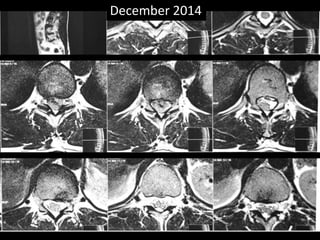

• A MRI was done.

• There was a disc extrusion at D10 – D11.

• The extruded fragment was on left side.

December 2014